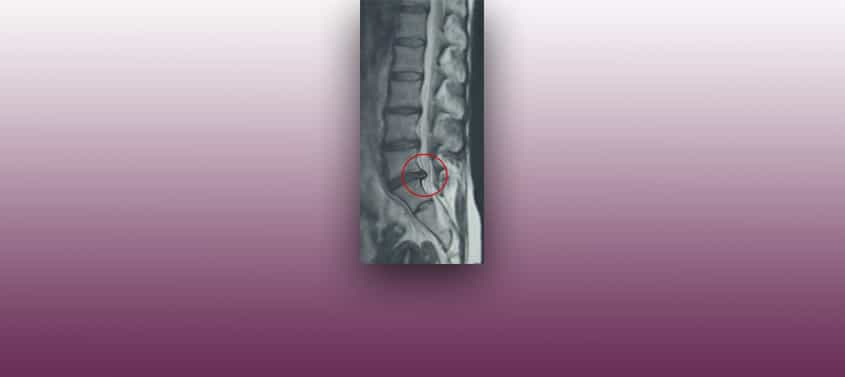

Идиопатический сколиоз

Последнее редактирование: 03/01/2019, Доктор Мигель Б. Ройо Сальвадор, Номер в коллегии: 10389. Нейрохирурга и Невролога. Определение Идиопатический сколиоз — боковое искривление позвоночника, которое происходит по неизвестной причине, чаще всего встречается у женского пола и чаще проявляется в период роста. Рисунок 5.- МРТ позвоночника с вертикальным разрезом: виден сколиоз, внутри позвоночного канала спинной мозг не следует […]